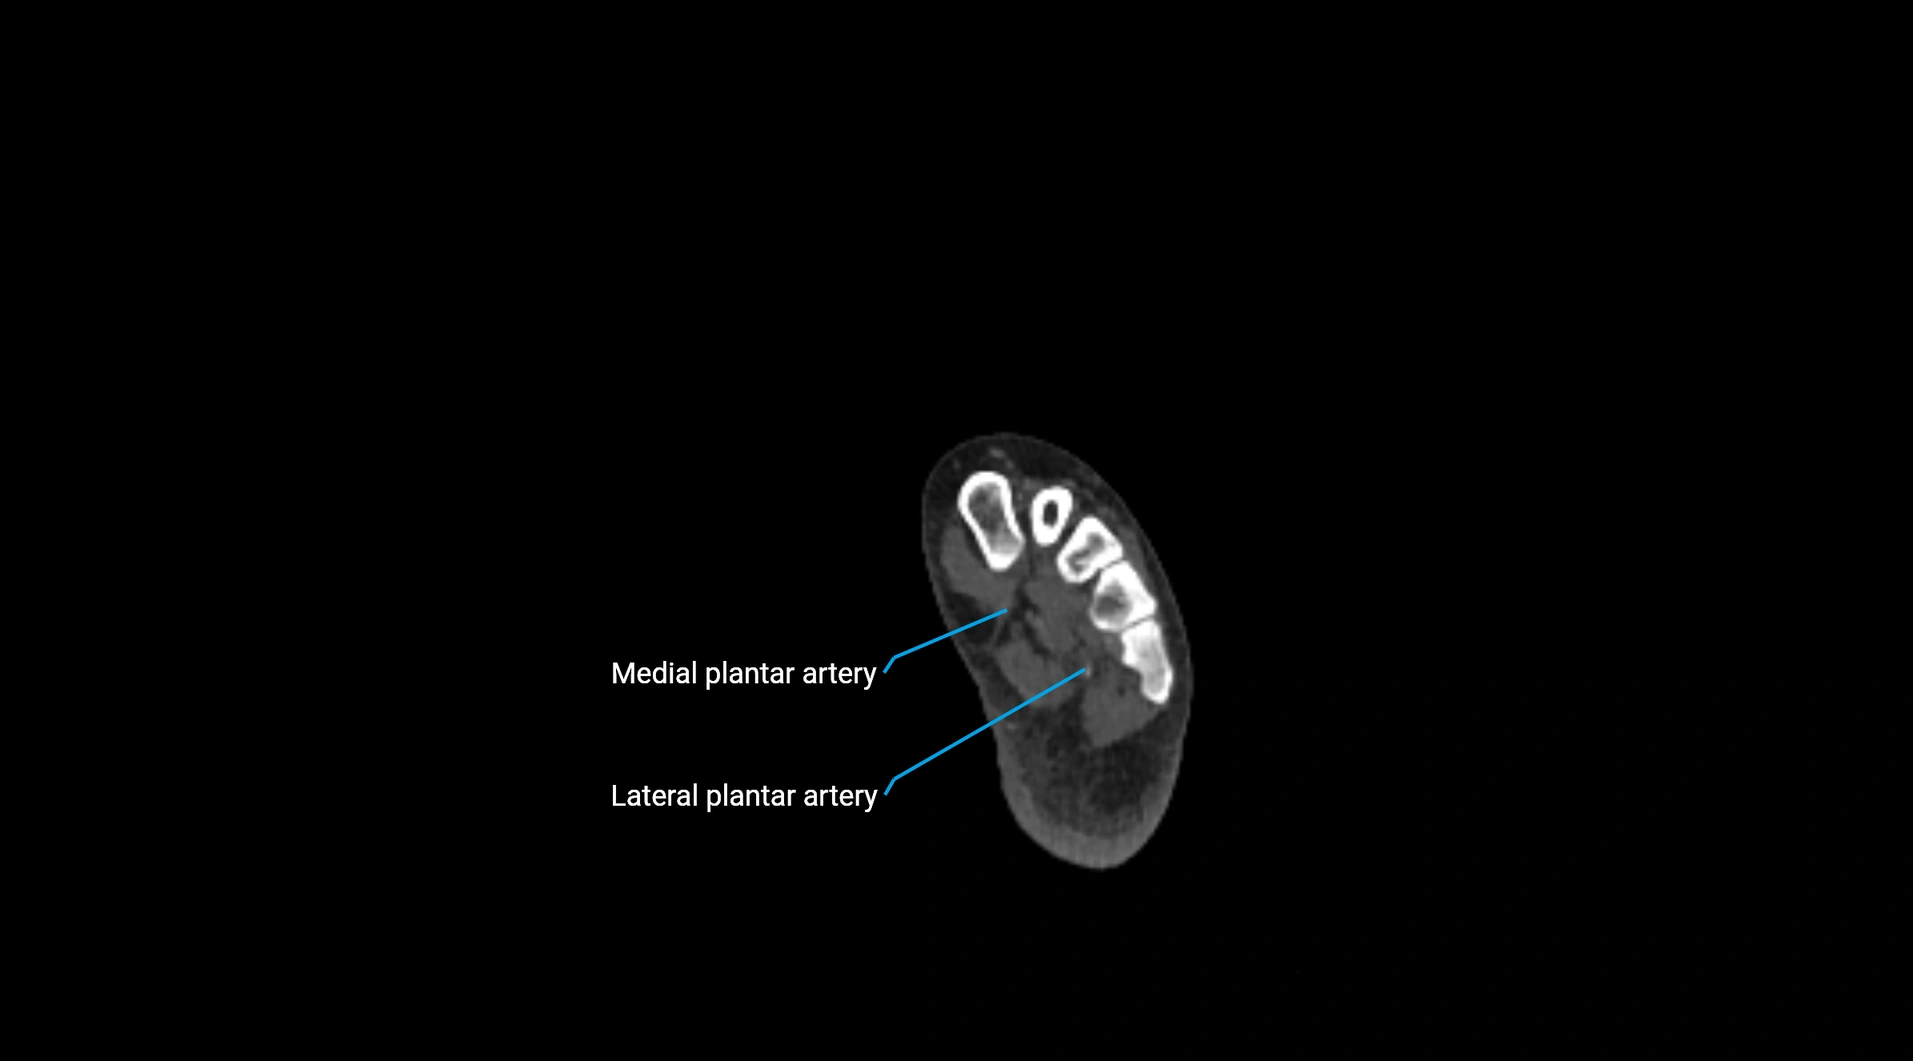

CT images

image